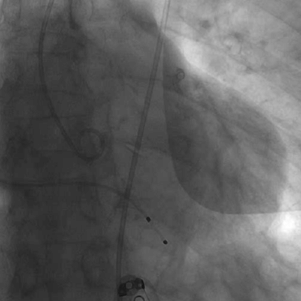

释放后造影结果

患者即刻跨瓣压差显著下降,再行主动脉造影提示瓣膜置入位置良好、形态完整,未见瓣周漏,未出现相关并发症,取得了良好的手术结果。